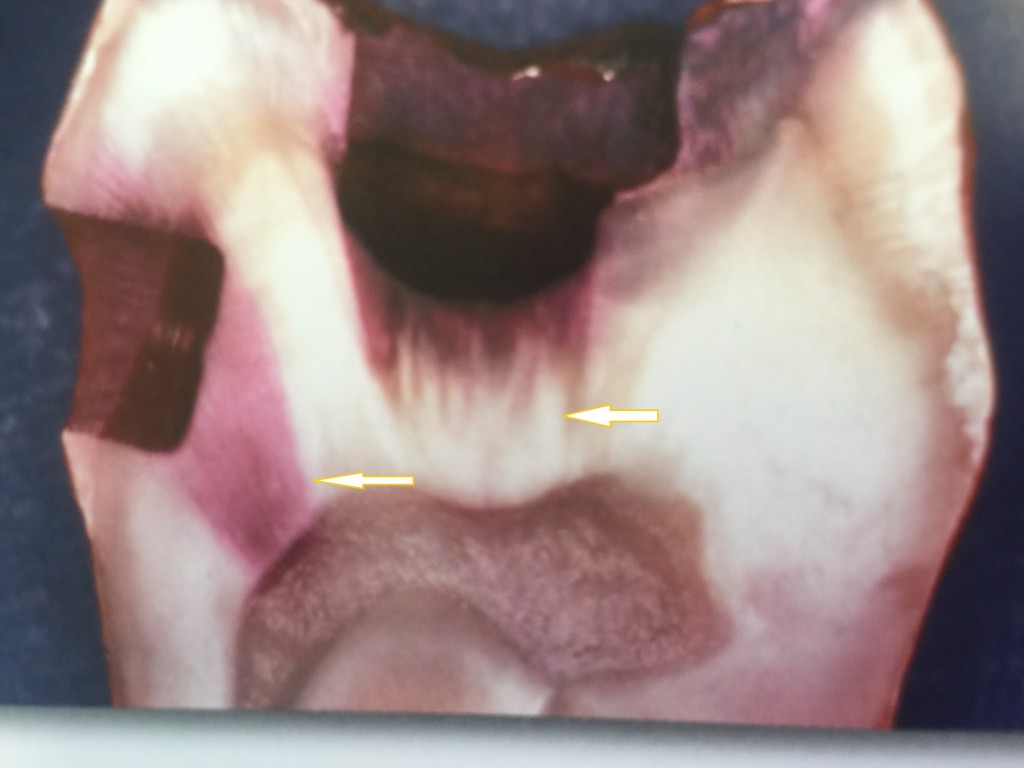

上の写真をご覧下さい。虫歯を持っている歯の病理切片です。(猪越重久先生著 1からわかるコンポジットレジン修復からコピー)

この写真は咬合面の虫歯に健全象牙質に及ぶ窩洞(頬側面)を形成し、色素液に浸漬しました。咬合面のう窩から侵入した色素はすべて透明象牙質で止まっていますが、健全象牙質まで形成した頬側面の窩洞では、色素が窩底から象牙細管を伝わり歯髄腔まで侵入しています。(教科書から引用)

写真の下に見える空洞が歯髄腔と言って神経、血管が存在していたところです。健康な歯質を削ると刺激が歯髄腔にまで及ぶということの証拠です。左の矢印ではが歯髄腔まで赤い色素が到達しているが、右の矢印の部分では透明層という部分で赤い色素は止まっている。健康な歯、象牙質を削ると後でしみるようになる証拠写真のようなものです。